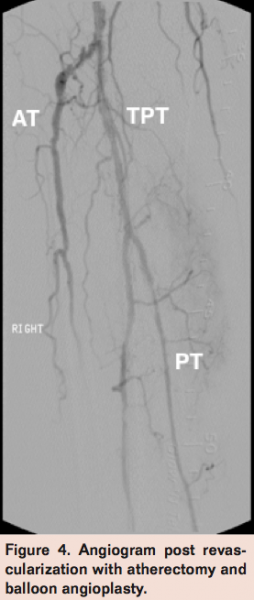

A second wire was then advanced into the PT artery and balloon angioplasty performed of the PT and peroneal arteries using a Coyote 2 x 220 mm balloon (Boston Scientific) with good angiographic result and brisk 2-vessel runoff into the right foot (Figure 4). The patient was discharged home the following day and returned for follow-up in 4 weeks with no residual symptoms, a completely healed ulcer, and improved ABI of 1.34.